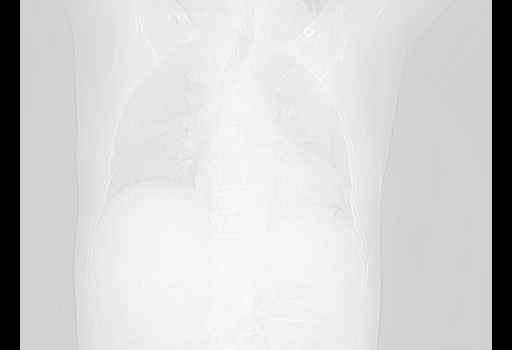

经过24天治疗,岳父的病情基本稳定。生活基本可以自理,可以下床活动。呼吸困难早已消失。体温基本正常。

特别感谢胡教授、高管、桃子版主给出关键的治疗建议。桃版把所有肺部影像和全部临床资料请所在医院呼吸科、感染病科、结核科、临床免疫科专家会诊。临床免疫科专家制定了完整的治疗方案。